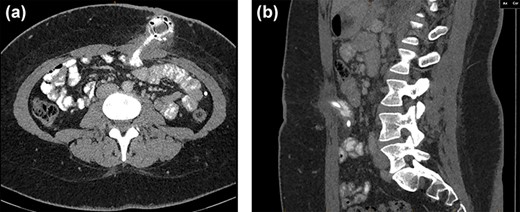

A 24 years old woman presented to ED with intermittent vague upper abdominal pain, nausea and malaise for 5 months. Her past history was only significant for obesity, for which she had an LAGB inserted over 4 years ago. Her blood tests on presentation revealed a white cell count of 8.46 109/L and a C-reactive protein of 28 mg/L with haemoglobin, platelets, electrolytes and liver enzymes all being within normal limits, as were her vitals. An abdominal examination revealed a focal tenderness over her periumbilical area and surrounding the well-healed LAGB port site. Computed tomography scan (Fig. 1a and b) showed an abnormal port position with soft tissue thickening seen surrounding the tube within the subcutaneous tissues of the abdominal wall and for a short distance within the abdomen and a segment of small bowel immediately deep to the entry. Findings were highly suspicious for a peritubal infection and/or a small-bowel perforation.

CT axial (a) and sagittal (b) views showing soft tissue thickening surrounding the LAGB port within the subcutaneous tissues of the abdominal wall extending to a segment of small bowel.